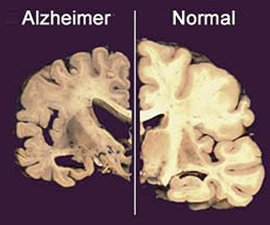

Alzheimer’s disease is characterized by the loss of neurons and synapses in the cerebral cortex and certain subcortical regions. This loss results in gross atrophy of the affected regions, including degeneration in the temporal and parietal lobes and parts of the frontal cortex and cingulate gyrus (Figure 2).

Figure-2- Brain atrophy in Alzheimer’s disease